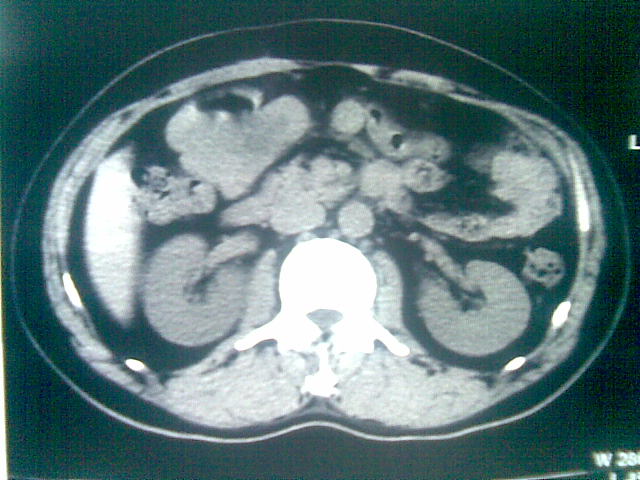

标题: CT23981:男,38岁阑尾炎术后透视胸腔积夜!做CT如下!积液包 [打印本页]

标题: CT23981:男,38岁阑尾炎术后透视胸腔积夜!做CT如下!积液包

可能与阑尾术后关系不太大,1.胸膜增厚粘连见少量气体。包裹脓气胸?左侧网膜囊脓肿?

.胸膜增厚粘连见少量气体。包裹脓气胸

少量积液部分粘连

左侧胸膜增厚、粘连+包裹液气胸。